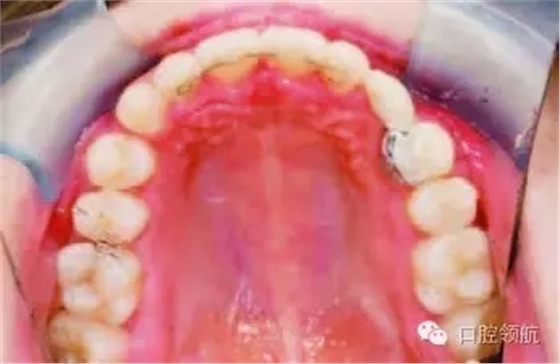

UL3采用樹脂粘結(jié)橋體修復(fù)(圖2.26),討論橋體的設(shè)計(jì)

圖2.26

這是單端懸空式橋體,依靠單一金屬臂連接至UL4腭側(cè)。單端懸空式橋體比雙端設(shè)計(jì)預(yù)后更好。雙端橋體未來失敗風(fēng)險(xiǎn)更高,因?yàn)橐粋?cè)基牙粘結(jié)失敗可能導(dǎo)致另一側(cè)基牙難以察覺的齲壞。因?yàn)閁L4腭側(cè)面積大于稍小的UL2,所以選作單端基牙。另外,金屬臂在光照下顯現(xiàn)的“透光效應(yīng)”對美觀的影響在這一區(qū)域相對也較小。

該病例中放置粘結(jié)式保持器的原理是什么?

治療前UL2扭轉(zhuǎn),扭轉(zhuǎn)牙易復(fù)發(fā),粘結(jié)式保持器可降低復(fù)發(fā)風(fēng)險(xiǎn)。圖2.27為最終牙合像。